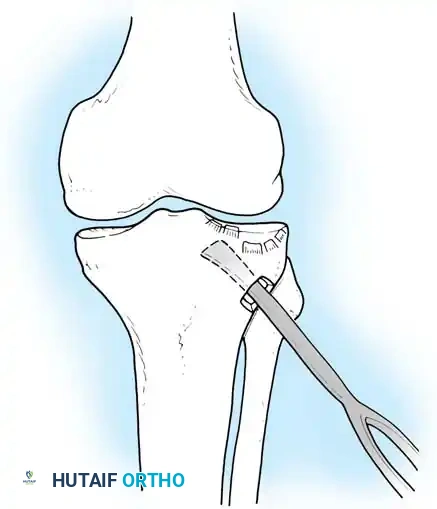

يتم اختيار الشق الجراحي بناء على موقع الكسر كما ظهر في الأشعة المقطعية.

النهج الجراحي للوصول إلى مفصل الركبة

المدخل الأمامي الجانبي يُستخدم لكسور الهضبة الخارجية، حيث يتم رفع الأنسجة بحذر للوصول إلى المفصل ورؤية الغضروف الهلالي وسطح العظم المكسور. أما المدخل الخلفي الداخلي فيُستخدم لكسور الهضبة الداخلية، ويتطلب وضعية خاصة للمريض للوصول الآمن للكسر بعيدا عن الأوعية الدموية.

رفع سطح المفصل المكسور أثناء الجراحة